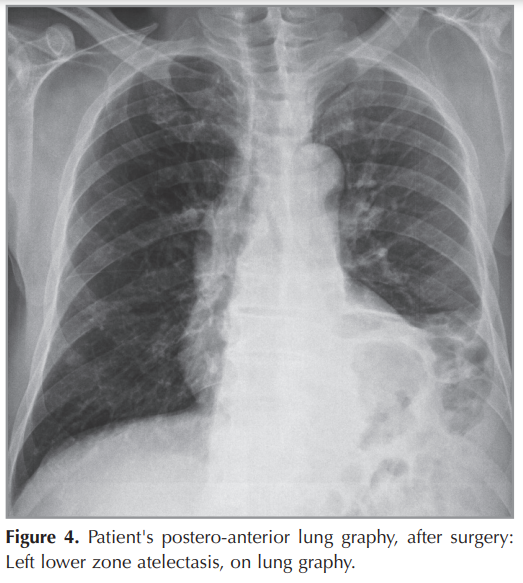

The patient is a 51-year old man, presented with shorthness of breath and cough for 1 months. Chest x-ray was normal (Figure 1). Chest CT scan showed a 30-25 mm heterogeneously enhanced mass lesion with well defined margin, In the left lower lobe of the lung (Figure 2). Bronchoscopy showed no endobronchial lesion. After the PET-CT, the patient was staged as cT2aN1M0 (Stage 2B) (Figure 3). He received video-assisted thoracoscopic surgery of left lower lobe of lung and mediastinal lymph nodes dissection ((Figure 4),(Figure 5)). His Ebv-Dna is Positive in blood tests. The pathology, immunohistochemical staining,and in situ hybridization results confirmed LELC of lung (Figure 6). Using in situ hybridization with exhibition of abundant EBV-encoded small nuclear RNA, in the majority of tumor cells is done. He received 4 cycles of induction chemotherapy with cysplatine and vinoralbine. The patient was discharged from hospital with close follow-up. No recurrence has been detected so far.

The patient is a 51-year old Turkish man, presented with shortness of breath and mild cough for 1 months. He has no chronic disease. Chest x-ray was normal (Figure 1). Chest CT scan showed a 30 × 25 mm heterogeneously enhanced mass lesion with well defined margin and lobulated contour, in the left lower lobe of the lung (Figure 2). Bronchoscopy showed no endobronchial lesion. Head and neck CT scan and nasopharyngeal fiberoscopy were performed and no obvious tumor was found. After the PET-CT, the patient was staged as cT2aN1M0 (Stage 2B), (Figure 3). He received video-assisted thoracoscopic surgery, of left lower lobe of the lung and mediastinal lymph nodes dissection ((Figure 4),(Figure 5)). His Ebv-Dna is Positive in blood tests. The pathology, immunohistochemical staining (Figure 6) and in situ hybridization results confirmed LELC of the lung. Using in situ hybridization with exhibition of abundant EBV-encoded small nuclear RNA, in the majority of tumor cells is done. Immunohistochemical staining was positive for cytokeratin (CK), a marker which was almost always positive in LELC of lung. He was discharged 10 days after the operation. He received 4 cycles of induction chemotherapy with cysplatine and vinoralbine. The patient had no postoperative complication and was discharged with the advice of chemotherapy. No recurrence has been detected so far.